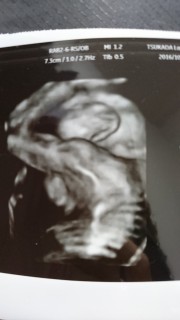

体外受精で授かりました。 いつも手を上げてるので、 お顔が見ずらいです(^^;; 1200gくらいあるらしくて、大きめベイビーです。 あくまで予測体重なので、経過観察だそうです(^^)